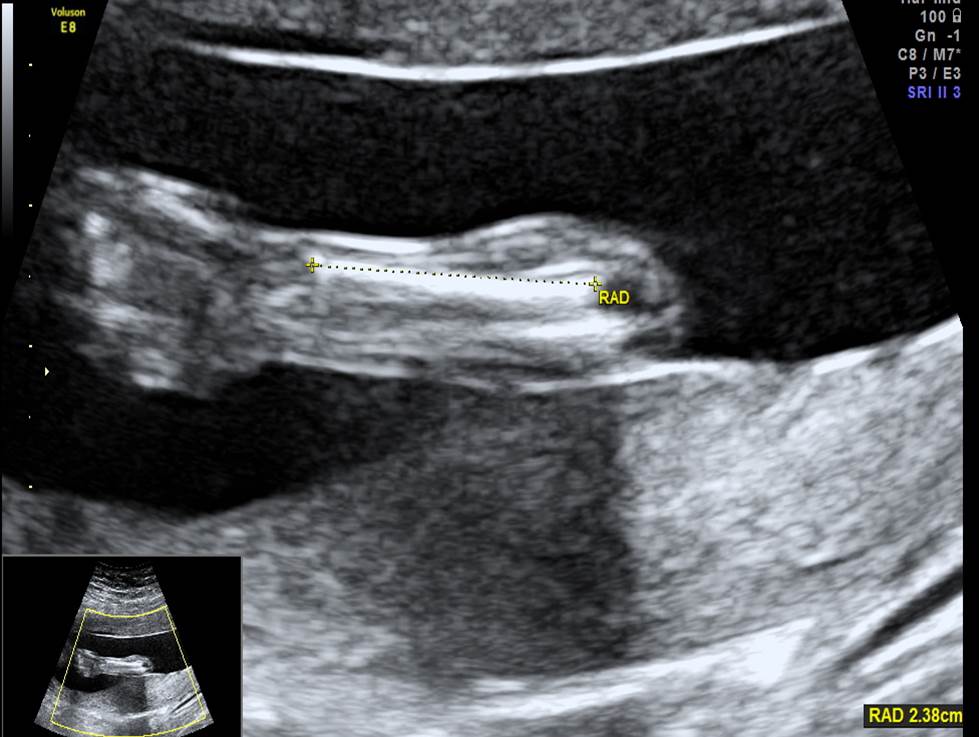

Проанализируйте изображения и видео-клипы плода в 20 недель, установите диагноз

Пациентка обратилась для получения второго мнения с диагнозом: беременность 20 недель, гипоспадия. Проанализируйте изображения и видео-клипы плода в 20 недель, установите диагноз